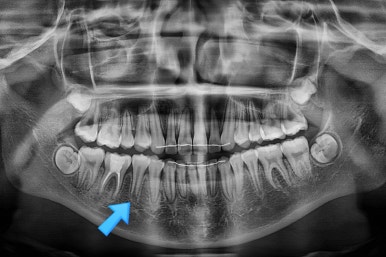

부산치아교정잘하는곳 키다리아저씨치과에 처음 오셨을 때의 X-ray 입니다.

해당 부위에 치아가 아래로 꺼져있고(가로 막혀서 나오지 못하고 있고) 주위 치아들이 기울어져 있는 것을 볼 수 있습니다.

원인 : 청소년기에 대부분의 공간문제는 "유치가 조기에 빠진 경우"